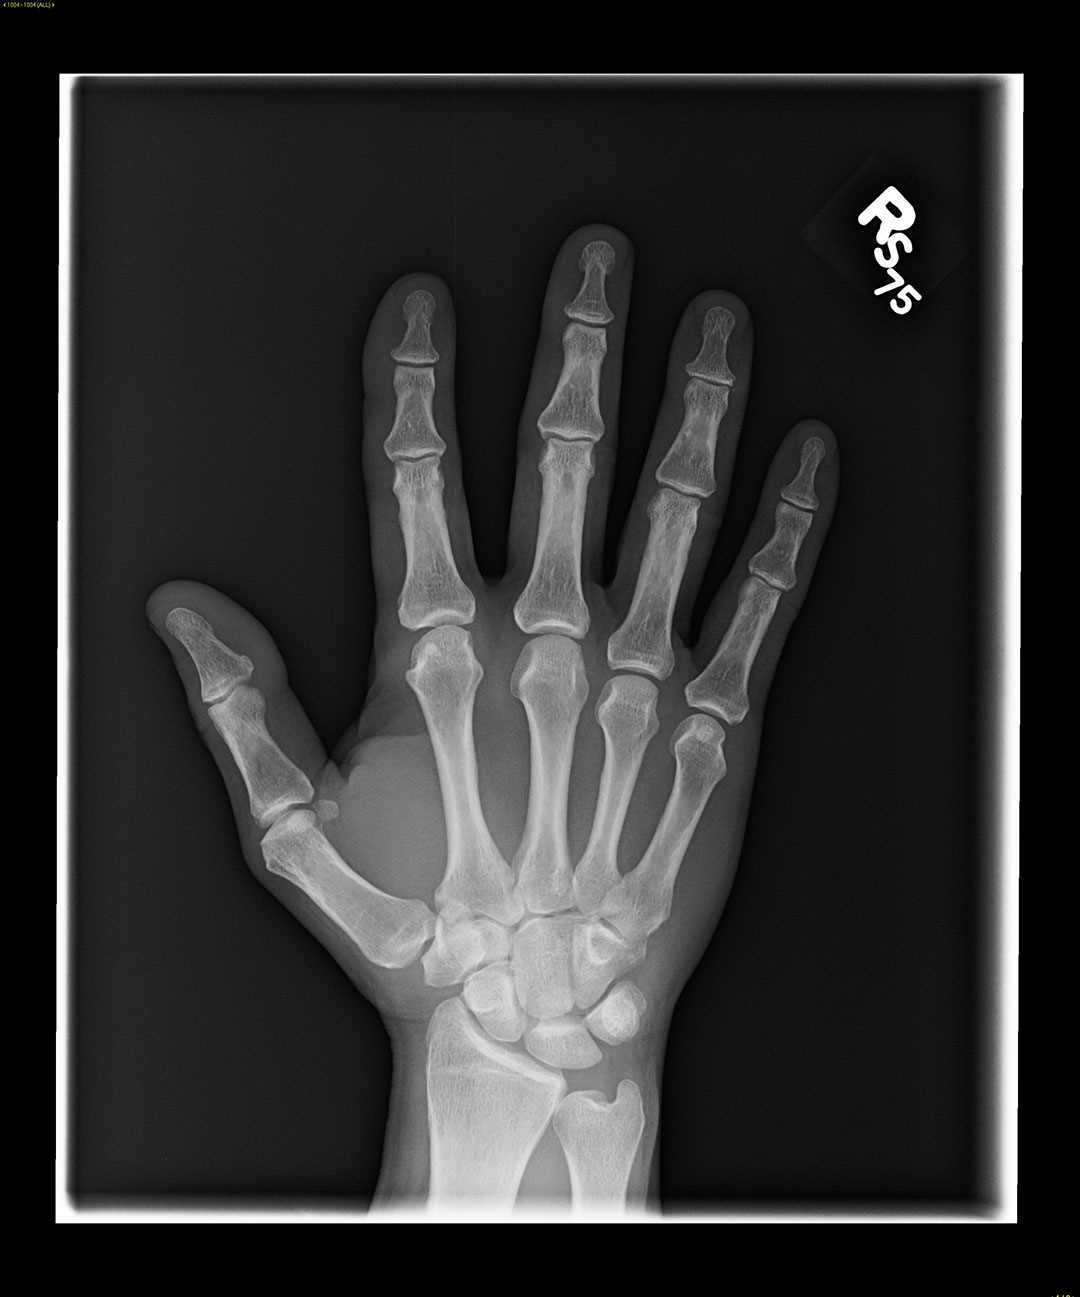

Triquetrum Fracture X Ray . Triquetral fracture is carpal bone fracture that generally occurs on the dorsal surface of the triquetrum. It may be fractured by means of. Although they are usually managed. Triquetral fractures are the most common carpal fracture after scaphoid fractures. Triquetrum fractures typically occur from a fall onto an outstretched arm with the wrist in extension and ulnar deviation, or in extreme. A triquetrum with a normal appearance. Diagnosis is confirmed with orthogonal views of the wrist. Triquetrum fractures are common carpal fractures that are often associated with other injuries to the wrist.

Although they are usually managed. Triquetral fracture is carpal bone fracture that generally occurs on the dorsal surface of the triquetrum. Diagnosis is confirmed with orthogonal views of the wrist. Triquetrum fractures typically occur from a fall onto an outstretched arm with the wrist in extension and ulnar deviation, or in extreme. It may be fractured by means of. Triquetral fractures are the most common carpal fracture after scaphoid fractures. A triquetrum with a normal appearance. Triquetrum fractures are common carpal fractures that are often associated with other injuries to the wrist.